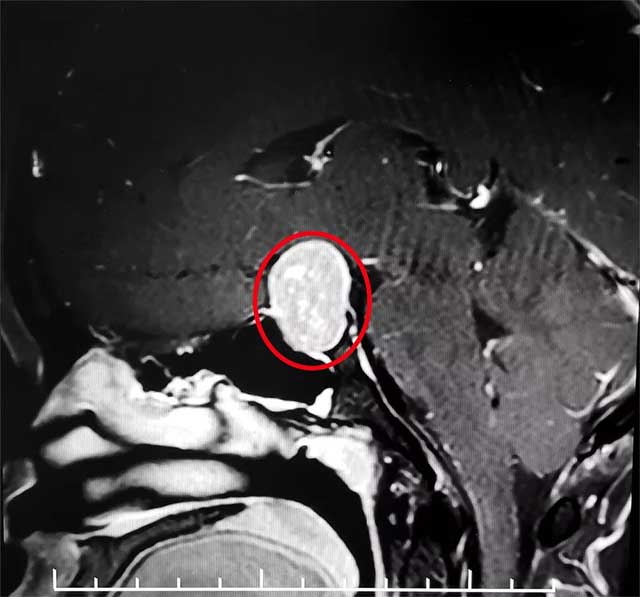

经头颅MRI检查,患者蝶鞍显著扩大,鞍区见一肿块影,大小约15*17*24mm,同时伴有视力减退、视野缺损。

6B病区潘仁龙主任指出,患者垂体瘤较大,属于垂体大腺瘤,已严重压迫视神经,手术指征明确,无明显手术禁忌,应及时手术,否则患者视力将严重受损。